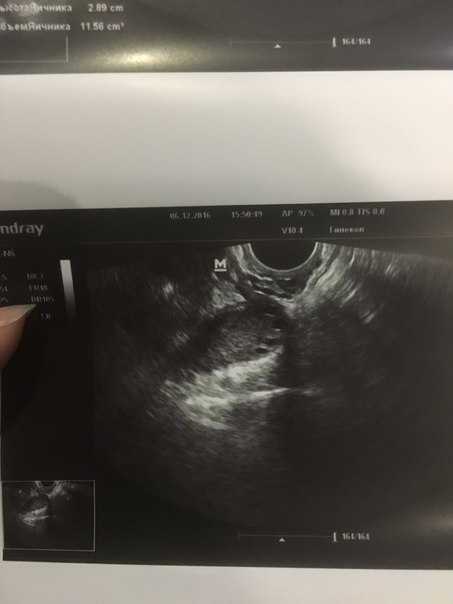

И эндометрий у меня 12 мм это толстенный эндометрий гиперплазия

Вот вам нормы эндометрия)))